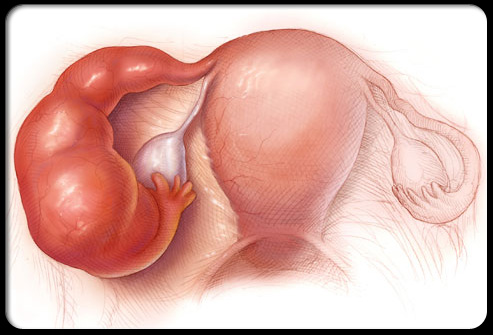

异位妊娠(宫外孕)

宫外孕指胚胎在子宫外着床发育,会导致尖锐的盆腔疼痛,通常出现在身体一侧,并可能伴有阴道出血、恶心和晕眩。宫外孕如果发现得足够早,是能够通过药物治疗的,但是如果出血或输卵管破裂,那么需要紧急手术治疗。